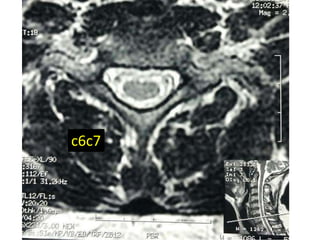

c6c7

47 year old woman with 6 month h/o neck stiffness and pain with

left UE paresthesias into

The elbow forearm and hand especially IF/thumb

Note:the black line directly posterior to the vertebral bodies and relative

Thinning of spinal cord, note normal disc height